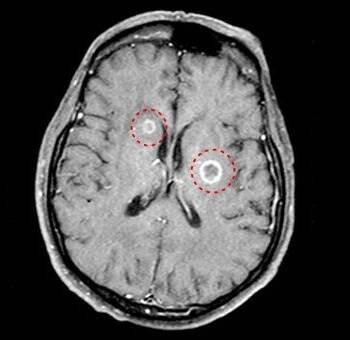

Mozkové metastázy jsou sekundární – druhotné nádory mozku, jejichž původem jsou nádory jinde v těle. Nejčastěji do mozku a míchy metastazují karcinom plic, ledvin, u žen karcinom prsu, a dále zhoubný melanom.

Funkční anatomie a neurologické projevy mozkových metastáz

Mozkové metastázy jsou častou komplikací systémových nádorových onemocnění, z nichž 60–75 % se v průběhu života stává symptomatickými.